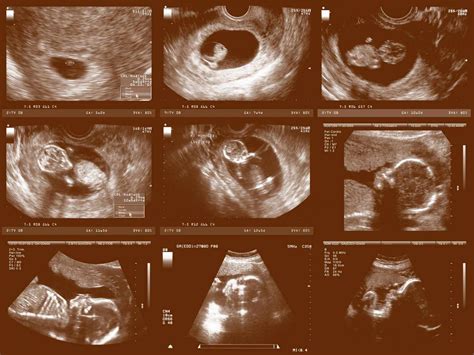

A sonogram is the image produced by ultrasound technology. It is essentially a visual representation of the internal structures of the body captured by ultrasound waves. Sonograms are used to diagnose a variety of conditions, including tumors, cysts, and other abnormalities. In the context of prenatal care, sonograms provide detailed images of the fetus, allowing healthcare providers to assess its development and detect any potential issues.

Sonograms can be performed at different stages of pregnancy, with each stage providing different insights. Early sonograms, often done around 6-8 weeks, can confirm the presence of a fetus and determine the gestational age. Later sonograms, typically around 18-22 weeks, offer more detailed images and can reveal the sex of the baby, as well as check for any structural abnormalities.